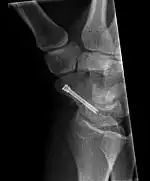

Scaphoid fracture before and after operation

The scaphoid can be slow to heal because of the limited circulation to the bone. Fractures of the scaphoid must be recognized and treated quickly, as prompt treatment by immobilization or surgical fixation increases the likelihood of the bone healing in anatomic alignment, thus avoiding mal-union or non-union.[6] Delays may compromise healing. Failure of the fracture to heal ("non-union") will lead to post-traumatic osteoarthritis of the carpus.[1]:189 One reason for this is because of the "tenuous" blood supply to the proximal segment.[3] Even rapidly immobilized fractures may require surgical treatment, including use of a headless compression screw such as the Herbert screw to bind the two halves together.

Healing of the fracture with a non-anatomic deformity (frequently, a volar flexed "humpback") can also lead to post-traumatic arthritis. Non-unions can result in loss of blood supply to the proximal pole, which can result in avascular necrosis of the proximal segment.

Scaphoid fractures may be difficult to diagnose via plain x-ray. A repeat x-ray may be required at a later date, as might cross-sectional imaging via MRI or CT scan.[6]